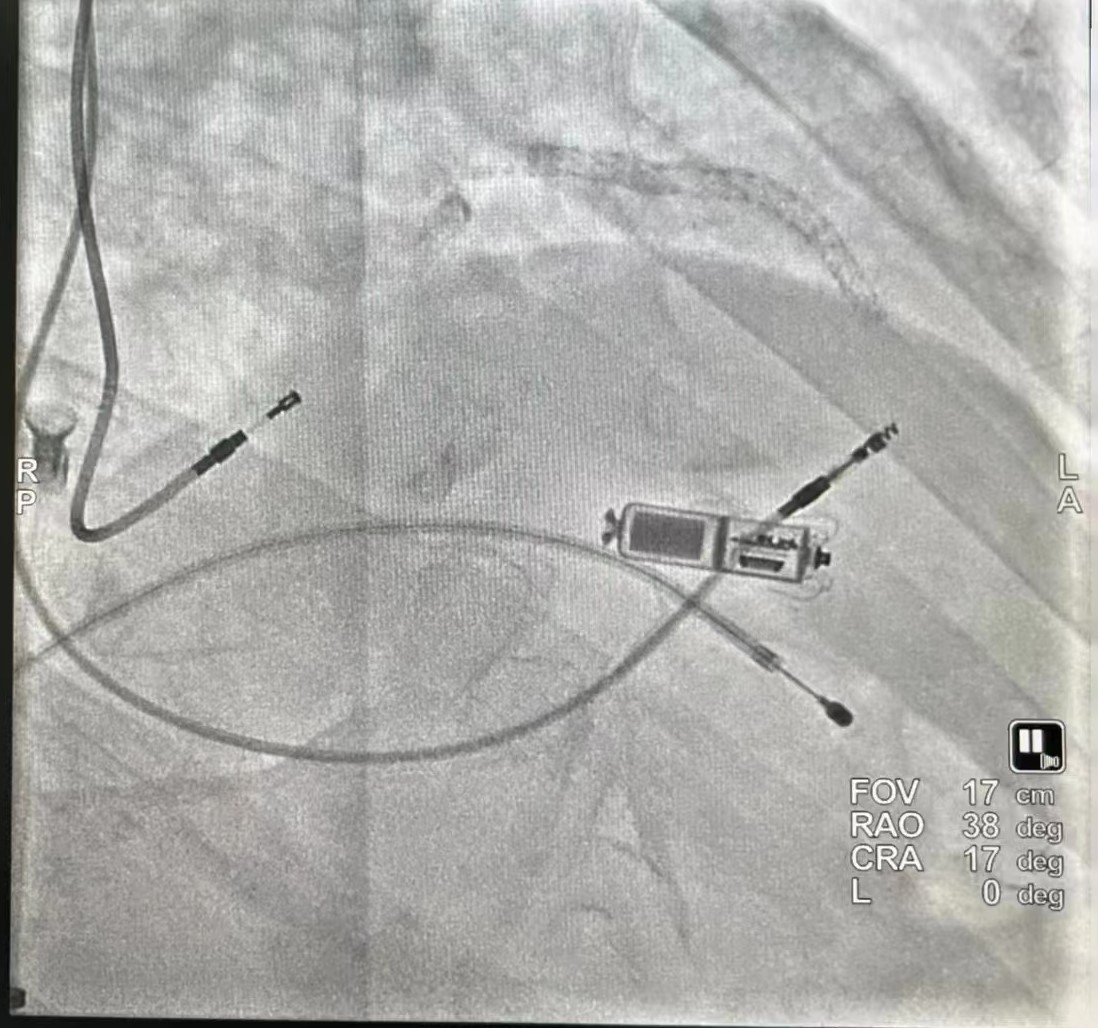

在临时起搏器保护下,穿刺右侧股静脉送Micra递送系统经右心房跨三尖瓣送抵中位间隔处,透视见电极贴壁良好,原位释放起搏器,行牵拉试验示起搏器固定良好,剪断栓绳后撤出输送鞘管,缝合伤口予以加压包扎。术程顺利,起搏器工作良好。术中更是留下了永久电极、临时电极、无导线起搏器、冠脉支架共现的场景!